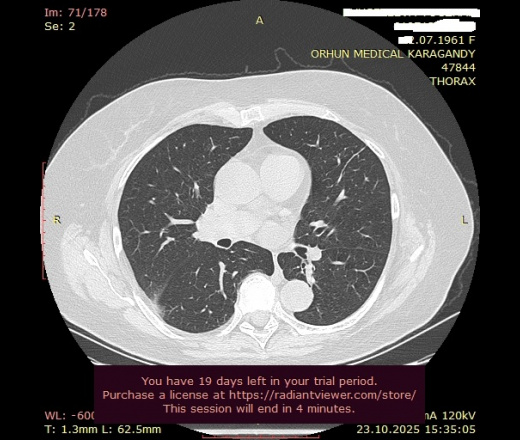

Может ли данный очаг (ТЭЛА?): "В верхней доле (S2) правого легокого, субплеврально по задней поверхности, участок уплотнения инфильтративного характера, плотностью 9HU, неправильной формы, размерами 3,2х0,7х4,8 см, с нечеткими неровными контурами, с признаками частичной консолидации легочной ткани" - вызвать то расширение легочного ствола, который Вы заметили?

Добрый день, уважаемый Мурат Максутович! Если коротко, то - может. А если описать данные изображения, как "участок субплевральной консолидации с нечеткими контурами, основанием прилежащей к плевре, перифокальное "матовое стекло", наличие бронхососудистых тяжей", так рука сама собой выведет "КТ-картина в большей степени соответствует ТЭЛА и инфаркту легкого (инфаркт-пневмонии), рек УЗИ вен нижних конечностей, КТ ОГК с в/в КУ), но вся эта стройная картина также может как подтвердиться, так и рассыпаться в результате дообследования

Если рассуждать в таком ключе, что невралгия и пневмония могут возникать от переохлаждения и сопоставить с тем, что вовлечена плевра (а от неё, соответственно, боль), то вполне укладывается в закономерность.

Кашля/температуры нет, потому что, как я уже писал, предполагаю процесс не острый, а в стадии неполного разрешения, а то и вовсе по типу организующейся пневмонии - видим подтягивание плевры в сторону нижней доли.

Второй версией предполагал инфарктную пневмонию, так как тоже отметил расширенный легочной ствол (опять же, визуально, так как замерить нет возможности без DICOM), но меня смутило то, что при ТЭЛА всё-таки прослеживается принадлежность изменений к сегментам, а здесь на границе междолевой плевры, что более характерно для воспалительных изменений.

Тем не менее, не исключаю возможное поражение двух сегментов при ТЭЛА + (в пользу этой версии) ТЭЛА также нередко сопровождает боль.

А корреляция между площадью поражения легочной ткани и расширением легочного ствола вовсе не обязательна.